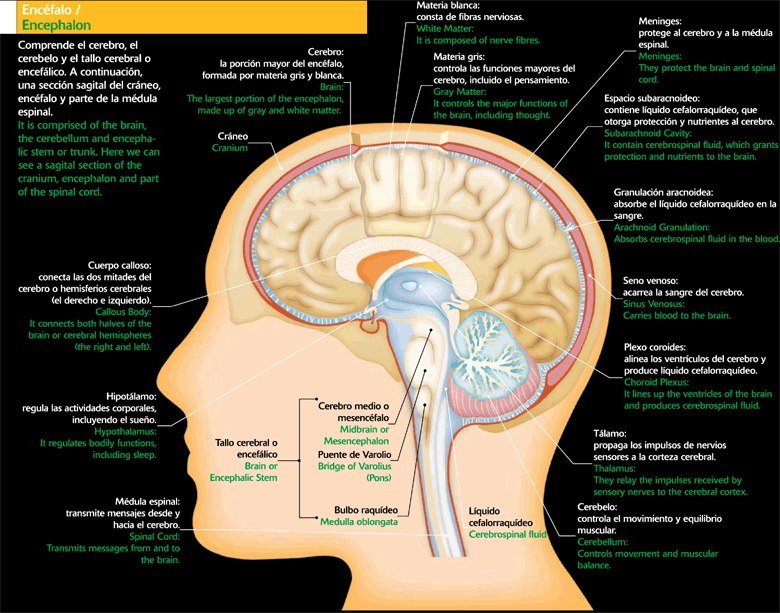

La cabeza

Se encuentra en la parte extrema superior del cuerpo. En su forma externa encontramos la cara y de manera interna encontramos el cerebro, el órgano que dirige a todo el cuerpo humano y que está protegido por el cráneo.

Sistema nervioso:

Es una red compleja de células y nervios por medio de los cuales se transmite información desde el cerebro y la médula espinal a las diferentes partes del cuerpo como por ejemplo el movimiento, sensaciones, etcétera.